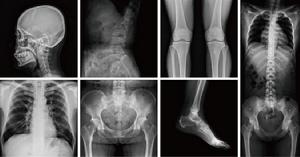

醫學用途(X射線)

倫琴發現X射線後僅僅幾個月時間內,它就被套用於醫學影像。1896年2月,蘇格蘭醫生約翰·麥金泰爾在格拉斯哥皇家醫院設立了世界上第一個放射科。

射線[具有特定能量的粒子或光子束流] 放射醫學是醫學的一個專門領域,它使用放射線照相術和其他技術產生診斷圖像。這可能是X射線技術套用最廣泛的地方。X射線的用途主要是探測骨骼的病變,但對於探測軟組織的病變也相當有用。常見的例子有胸腔X射線,用來診斷肺部疾病,如肺炎、肺癌或肺氣腫;而腹腔X射線則用來檢測腸道梗塞, 自由氣體(free air,由於內臟穿孔)及自由液體。某些情況下,使用X射線診斷還存在爭議,例如結石(對X射線幾乎沒有阻擋效應)或腎結石(一般可見,但並不總是可見)。

藉助計算機,人們可以把不同角度的X射線影像合成成三維圖像,在醫學上常用的電腦斷層掃描(CT掃描)就是基於這一原理。

X射線穿透能力與其頻率有關,利用其容易被高原子序數材料吸收的特點,防護上一般可用2-3mm左右的鉛板加以禁止。